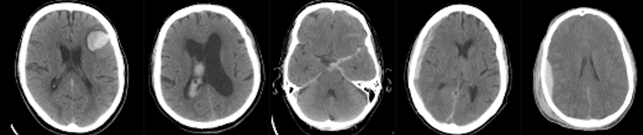

Intracranial hemorrhage (ICH) is a life-threatening emergency with high rates of mortality and morbidity. Rapid and early detection of ICH is essential because nearly 30% of the life loss happens in the first 24hours.The diagnosis of ICH is performed using CT brain scans (see Figure 1) that consist of multiple slices (typically ~35 per scan). This process requires the fast and accurate examination of a radiologist. In order to prompt the optimal treatment to patients in short time, computer-aided diagnosis (CAD) is being designed to establish a better triaging protocol.

Figure 1: Five slices of a CT brain scan for hemorrhage detection.